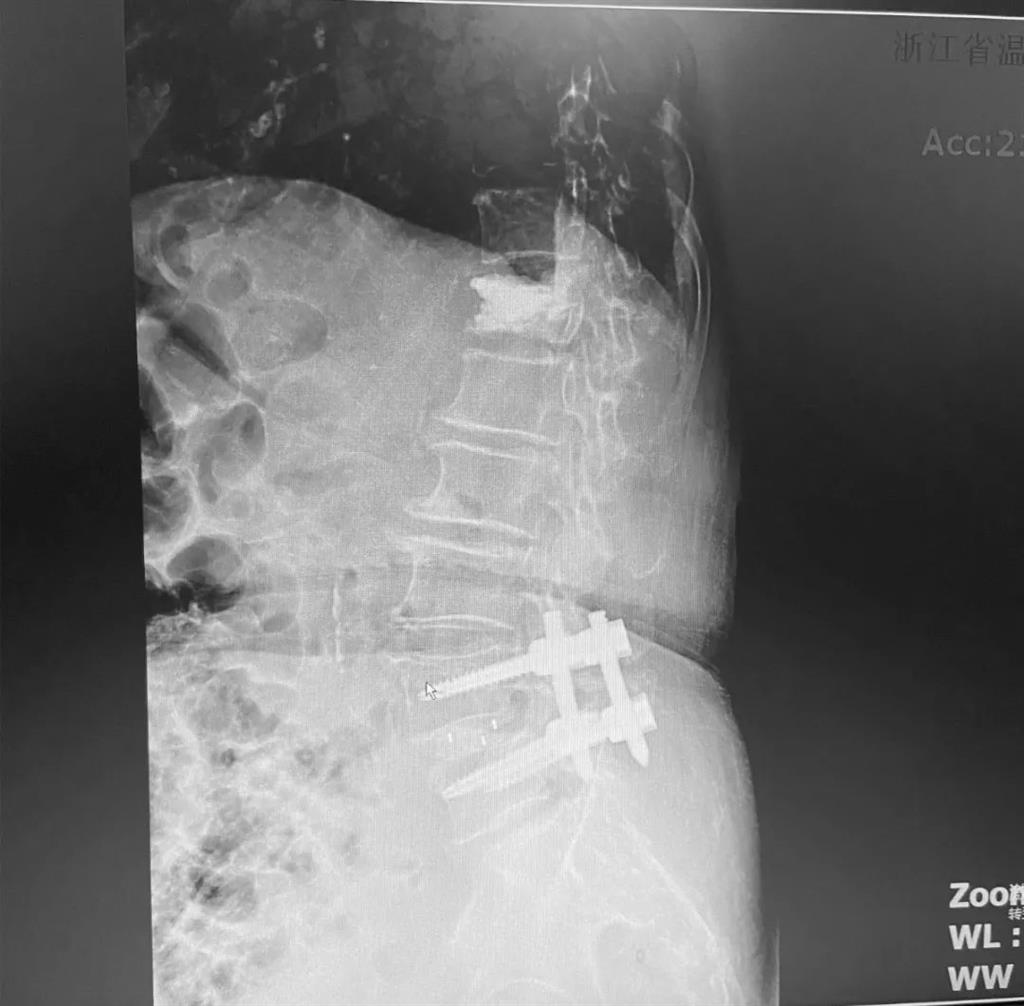

據(jù)了解,脊柱內(nèi)鏡下腰椎融合術(shù)只需要打幾個“鑰匙孔”即可完成。聽起來是不是很簡單?在脊柱內(nèi)鏡下,劉丹主任先后為患者進(jìn)行了椎管減壓、椎間盤摘除,再實(shí)施椎弓根螺釘放置、椎體植骨融合內(nèi)固定,一系列步驟有條不紊。

看似簡單的幾個步驟,但實(shí)際上很復(fù)雜,需要主刀醫(yī)生有豐富的手術(shù)經(jīng)驗(yàn)和細(xì)致耐心的操作。

而脊柱內(nèi)鏡下腰椎融合術(shù),作為目前國內(nèi)脊柱微創(chuàng)領(lǐng)域大力發(fā)展的新技術(shù),徹底改變了傳統(tǒng)開刀椎板切除椎間植骨融合內(nèi)固定的大創(chuàng)傷現(xiàn)狀,可以在較大程度上減少對脊柱后方穩(wěn)定結(jié)構(gòu)的破壞,創(chuàng)傷小,出血少,術(shù)后恢復(fù)快。

非常適用于體質(zhì)較差不能耐受開放手術(shù)的老年患者,且手術(shù)全程均在內(nèi)鏡監(jiān)測下進(jìn)行,能夠最大程度地避免硬膜囊和神經(jīng)根損傷,手術(shù)安全性更高。

術(shù)中只需切開4個如“鑰匙孔”般大小的孔道